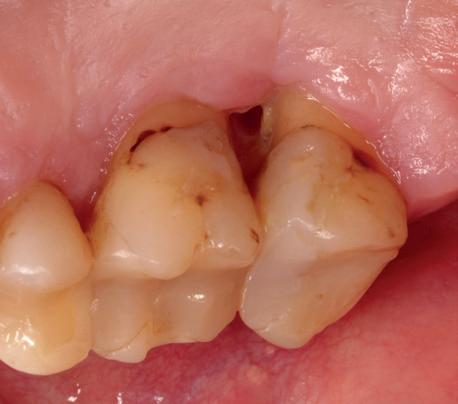

Casus

In deze casus is extractie van de 37 geïndiceerd in verband met een fistel en restpockets, zoals zichtbaar op de röntgenfoto’s (afbeelding 1). Duidelijk te zien is de forse peri-apicale ontsteking en het botverlies bij de 37, dat zowel richting buccaal als linguaal doorloopt. De 37 wordt atraumatisch verwijderd. Er is aan de linguale zijde veel bot verloren en er is sprake van een perforatie aan de buccale zijde.